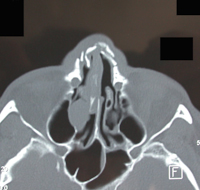

Aspects scannographiques de factures du nez